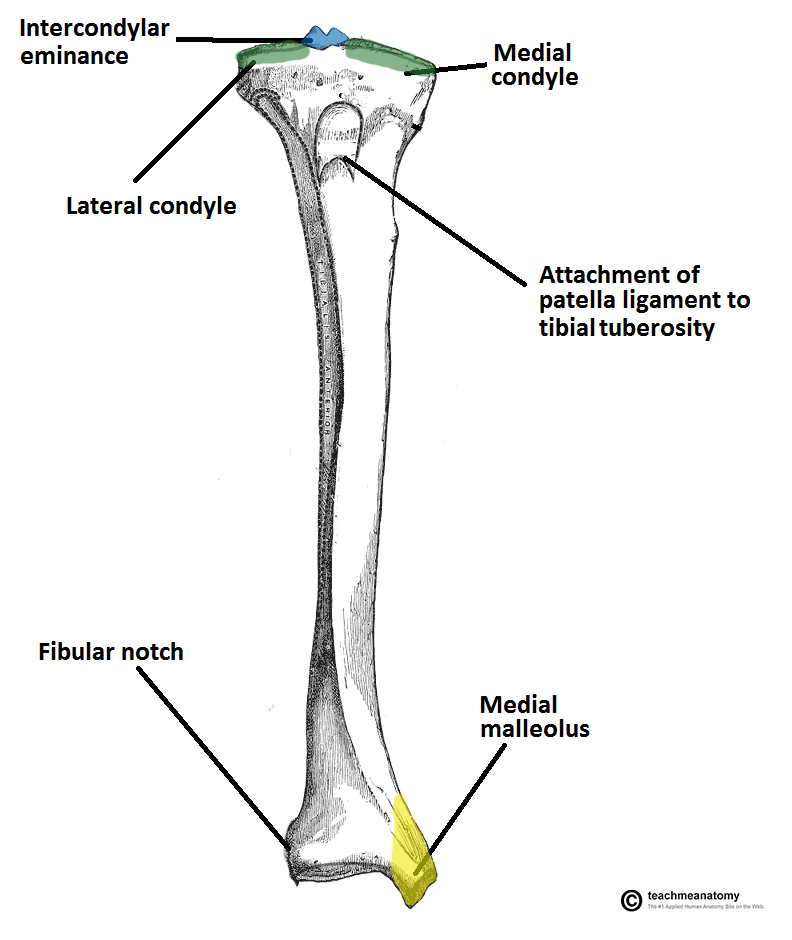

What is the tibia widened by at the proximal end? (Bony Landmarks)

Medial and Lateral condyles

The condyles form a flat surface known as what?

The Tibeal Plateau

What is the region between the condyles called?

Intercondylar Emimance

Two tubercles and a roughened area

Site of attachment for the ligaments and the menisci of the knee joint

The tibial intercondylar tubercles fit into what on the femur?

Intercondylar Fossa

What is on the anterior surface of the proximal tibia, inferior to the condyles?

Tibial Tuberosity

Patella Ligament

What is the name given to the bony projection that continues inferiorly on the medial side?

The Medial Malleolus

Laterally on the distal end is a notch. What is it known as and what is bound here?

Known as the fibular notch

Tibia and Fibula are bound